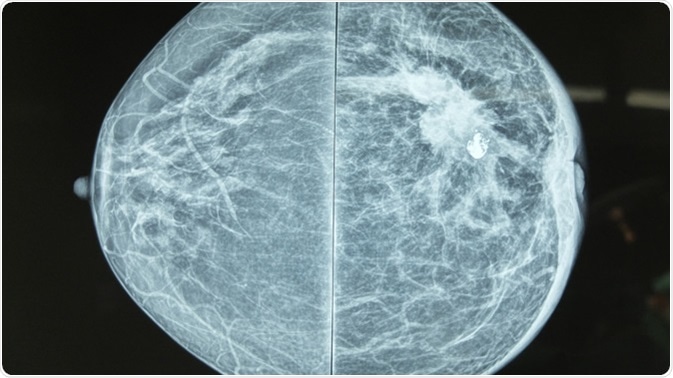

Mammography is a radiographic method which uses low-dose X-rays to image the breast tissue for both screening and diagnosis of breast cancer. Any suspicious high density regions or unusual patterns such as microcalcifications are examined carefully. These could be due to a range of abnormalities, such as tumors (benign and malignant), fibroadenomas, or cysts with solid areas.

Mammography image showing left breast calcification to suggest malignancy. Image Credit: Casa Nayafana / Shutterstock

A good mammogram requires firm breast compression against the detector. This minimizes breast movement and allows for the clearest image, it also provides the shortest distance between the breast and detector at all points, reducing the number of films and radiation exposure, while allowing single-plane imaging of the whole breast.